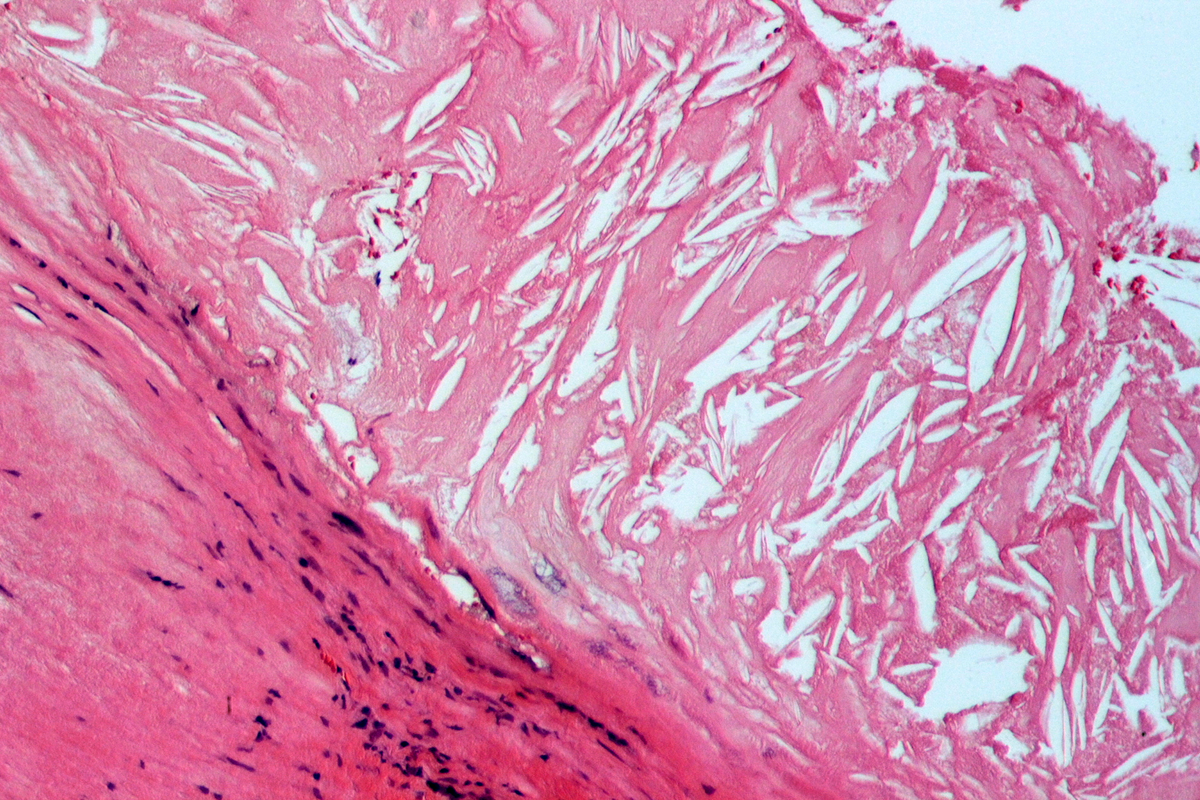

Высокий уровень холестерина в крови (гиперхолестеринемия) способствует образованию атеросклеротических бляшек.

Кристалы холестерина в атеросклеротической бляшке